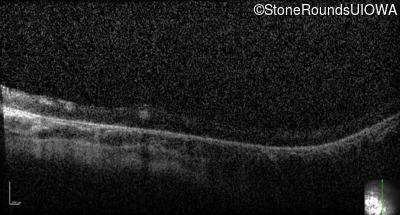

Optical Coherence Tomography - Right - Light Perception

Exemplar

Optical Coherence Tomography - Left - Light Perception